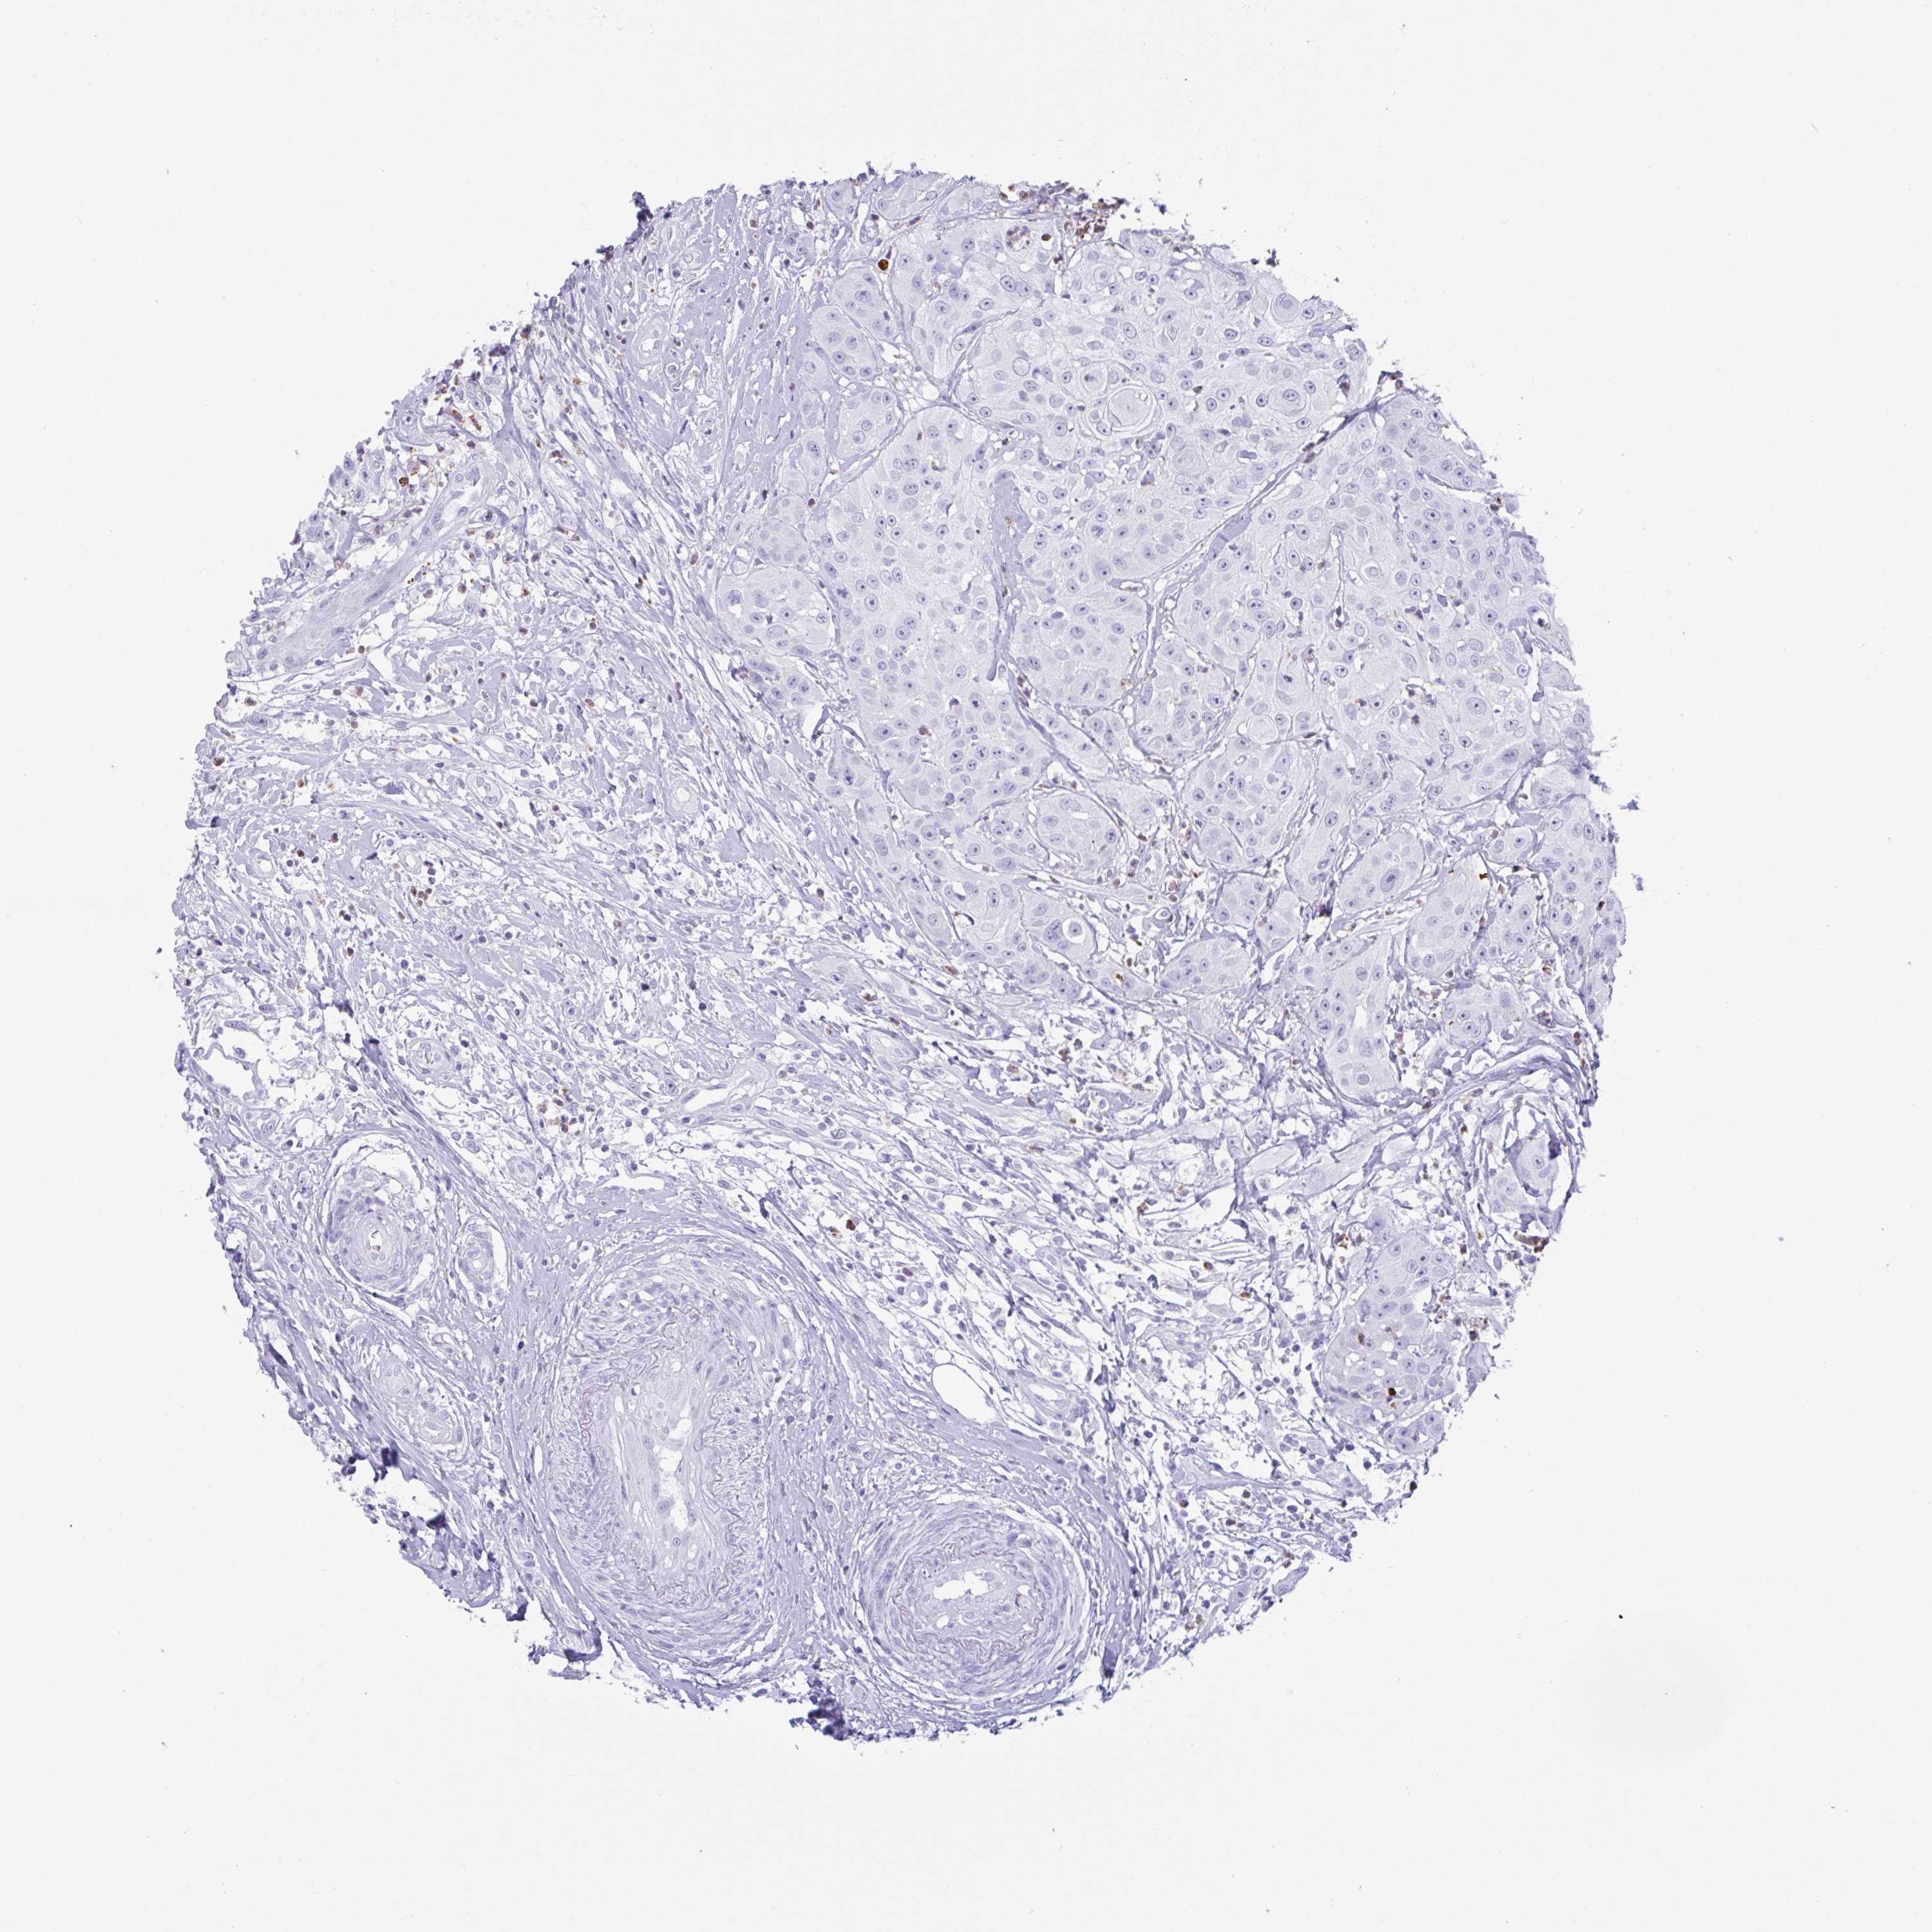

HEAD AND NECK CANCER - Protein expressioni

A mouse-over function shows sample information and annotation data. Click on an image to view it in a full screen mode. Samples can be filtered based on level of antibody staining by selecting one or several of the following categories: high, medium, low and not detected. The assay and annotation is described here.

Antibody stainingi

Antibody staining in the annotated cell types in the current human tissue is reported as not detected, low, medium, or high, based on conventional immunohistochemistry profiling in selected tissues. This score is based on the combination of the staining intensity and fraction of stained cells.

Each image is clickable and will lead to virtual microscopy that enables deeper exploration of all samples and also displays staining intensity scores, fraction scores and subcellular localization as well as patient and tissue information for each sample.

Antibody HPA053173

Staining

High

Medium

Low

Not detected

Intensity

Strong

Moderate

Weak

Negative

Quantity

>75%

75%-25%

<25%

None

Location

Nuclear

Cytoplasmic/membranous

Cytoplasmic/membranous,nuclear

Squamous cell carcinoma, NOS